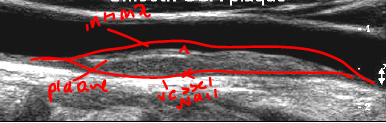

what type of plaqe is this?

smooth CCA plaque

what type of plaque morphology is this?

irregular, complex